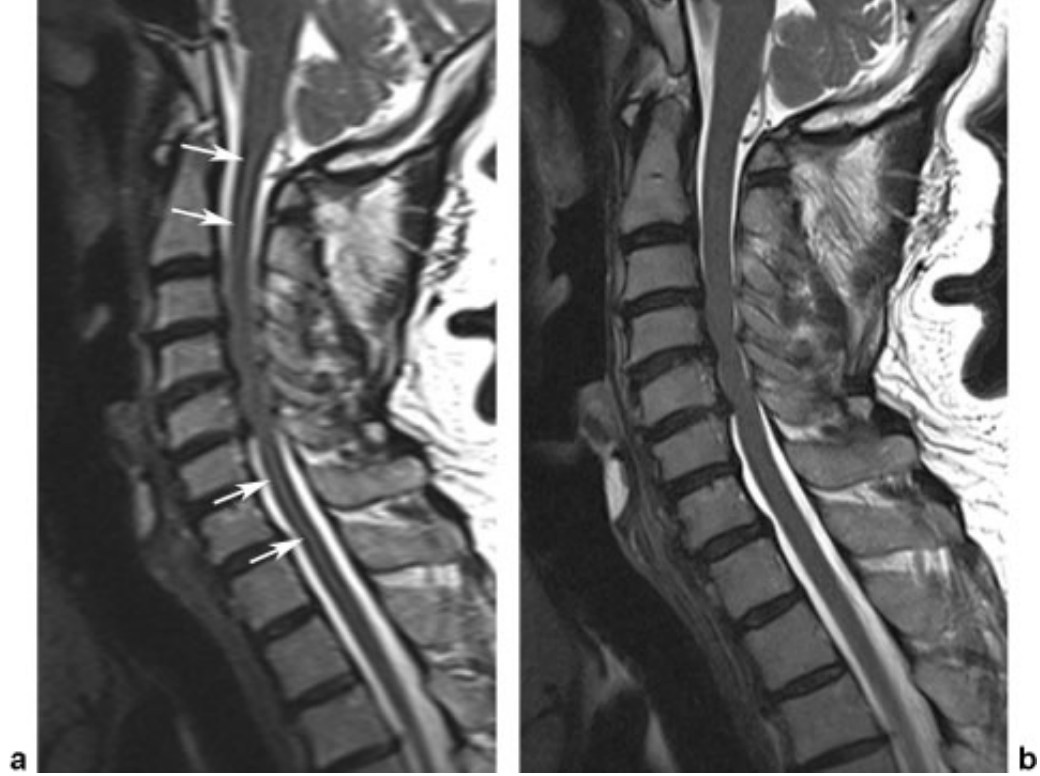

脑脊液流动伪影常易误诊为病变,需与椎管内占位相鉴别。如脊髓背侧脑脊液中可见多个不连续的低信号区,在不同序列成像中表现不同,有时可通过梯度回波 T2 加权像消除此伪影。

运动伪影由心脏和患者运动引起,像颈部吞咽动作引起的伪影可能被误认为脊髓病变,添加颈前饱和带可抑制。